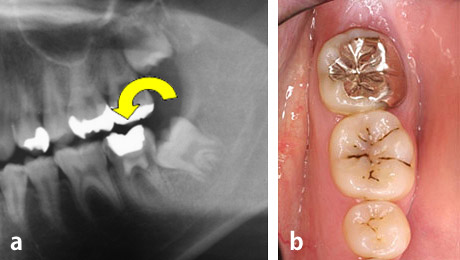

a、b: 治療前。16歳、少女。

第二大臼歯が吸収を受けており保存が不可能でした。そこで、隣接する親知らずを同部へ移植することにしました。